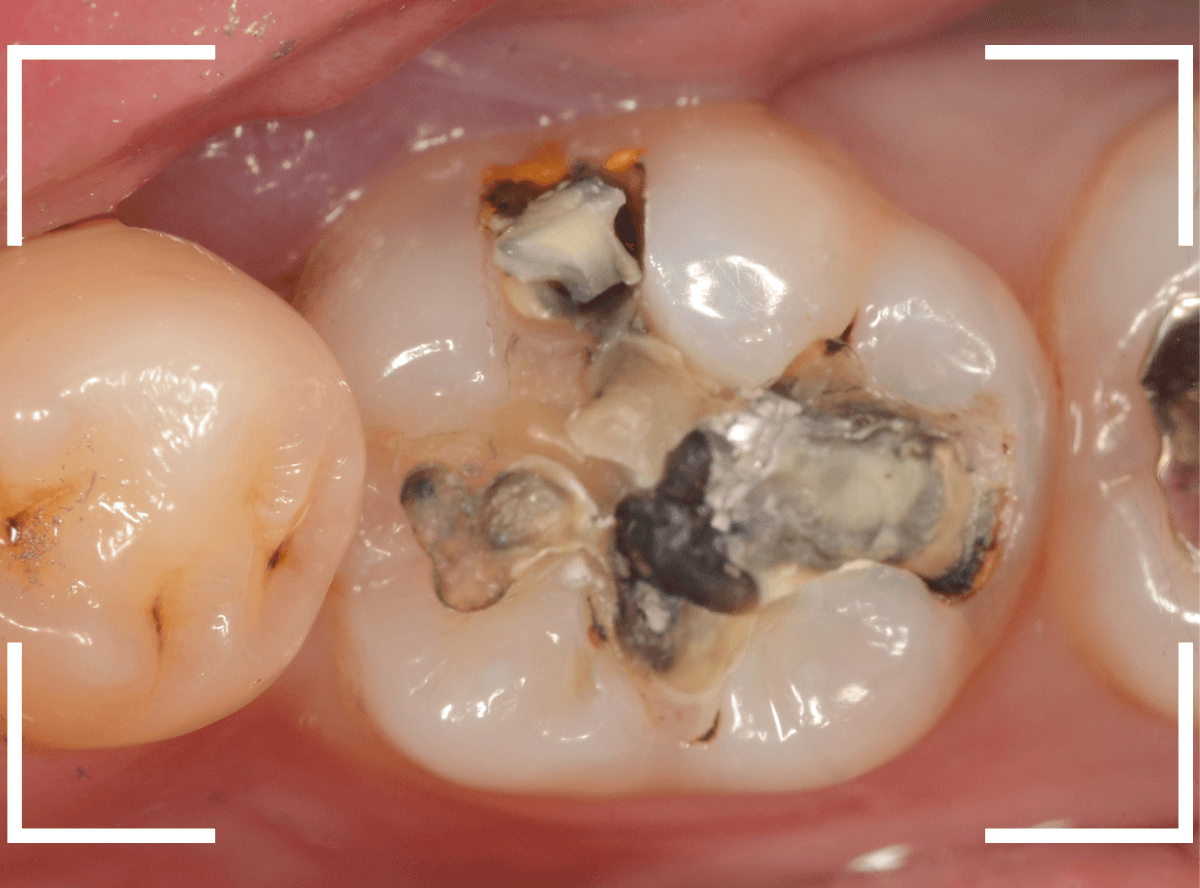

Case.8 大きな虫歯なのに、レントゲンではっきり写らない

こちらも定期検診希望で来院された患者さんです。

お口の中を拝見すると、明らかに虫歯がありました。

3本虫歯になっており、特に中央の小臼歯はかなり大きな虫歯になっているのが予想されます。

治療前にレントゲン写真で虫歯の大きさを確認するつもりが・・・あまりはっきり写ってきません。

患者さんに状況を説明して、歯を少しずつ削りながら虫歯を確認する事になりました。

まず、一番大きな虫歯と思われる部分を小さく削って確認します。

予想通り、虫歯が見えてきました。

隣りの奥歯と一緒に虫歯の治療を進めます。

色が染まっているところがまだ虫歯が残っている部分です。

2本とも、虫歯を全て取り切りました。

特に手前の歯はかなり広めの虫歯になっていました。

最終的に、手前の虫歯の除去も終わったところです。

手前の歯の虫歯は中央の歯まで達していました。

このように明らかに大きな虫歯があると診断されるような状況でも、レントゲン写真でうまく診断できない場合もあります。